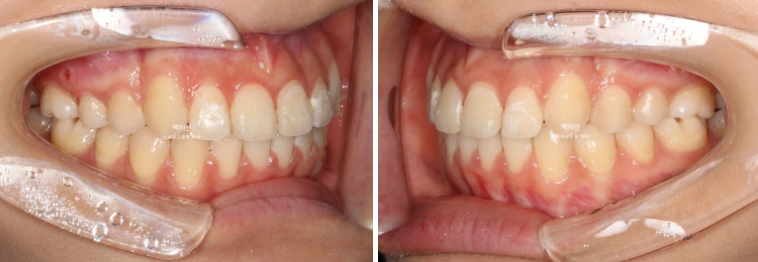

23.05~25.07

2년 전 5월, 인비절라인 교정을 위해 내원한 환자분입니다.

23.05

송곳니 덧니가 심한편입니다.

25.07

교합은 좌우 정 1급을 달성했으며 좋습니다.

좌 : 치료 전 / 우 : 치료 후